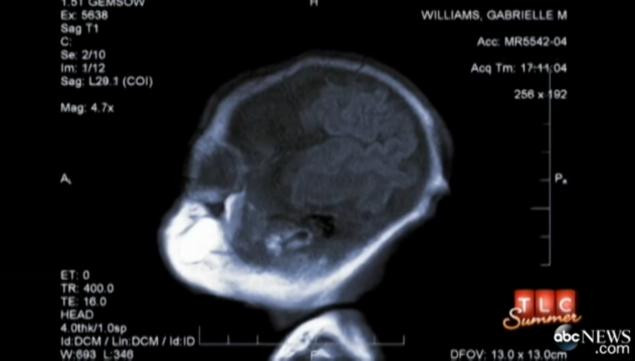

Gabby Williams, de 8 ani, cantareste doar 5 kilograme. Fetita plapanda, din Montana, Statele Unite, inca arata ca un bebelus si are nevoie de ingrijire asemenea unui nou nascut, mama si tatal ei schimbandu-i scutecele si hranind-o de mai multe ori pe zi.

Mama, Mary Margret William, a declarat pentru ABC News, ca fiica ei nu s-a schimbat aproape deloc de-a lungul anilor.